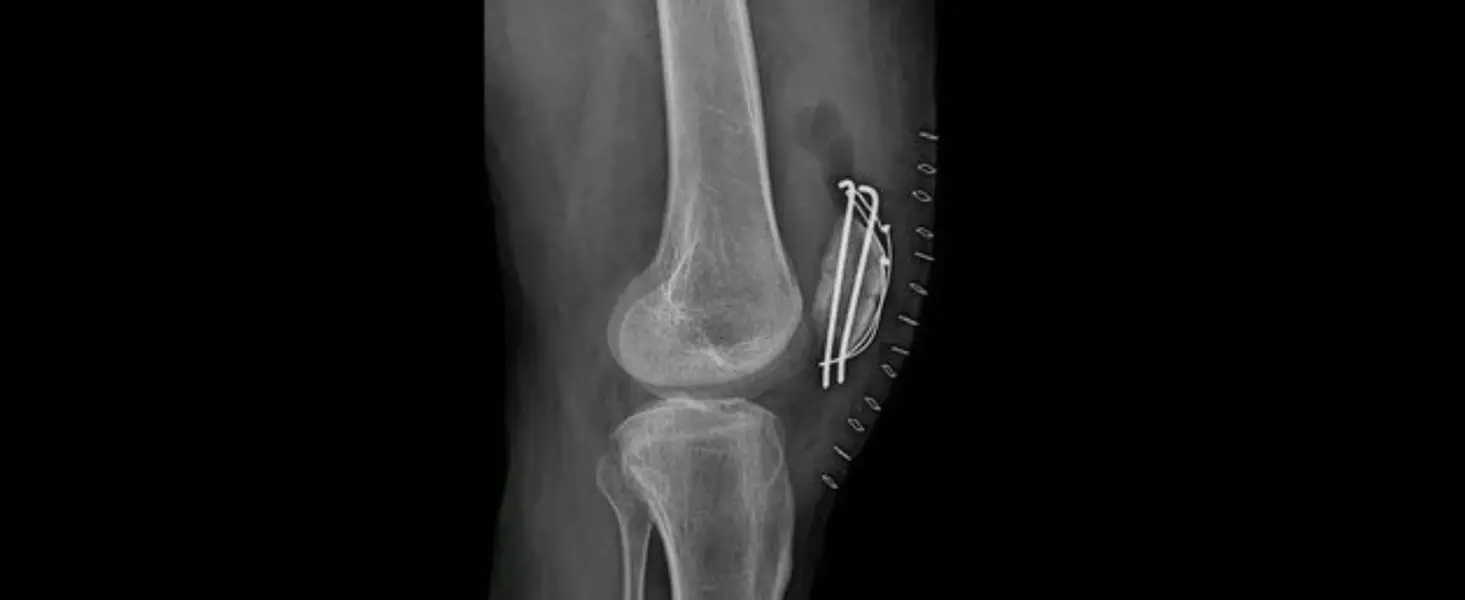

Frattura del Piatto Tibialestaff@2026-03-10T09:56:47+00:00 Frattura del Piatto Tibiale Chirurgia Traumatologica